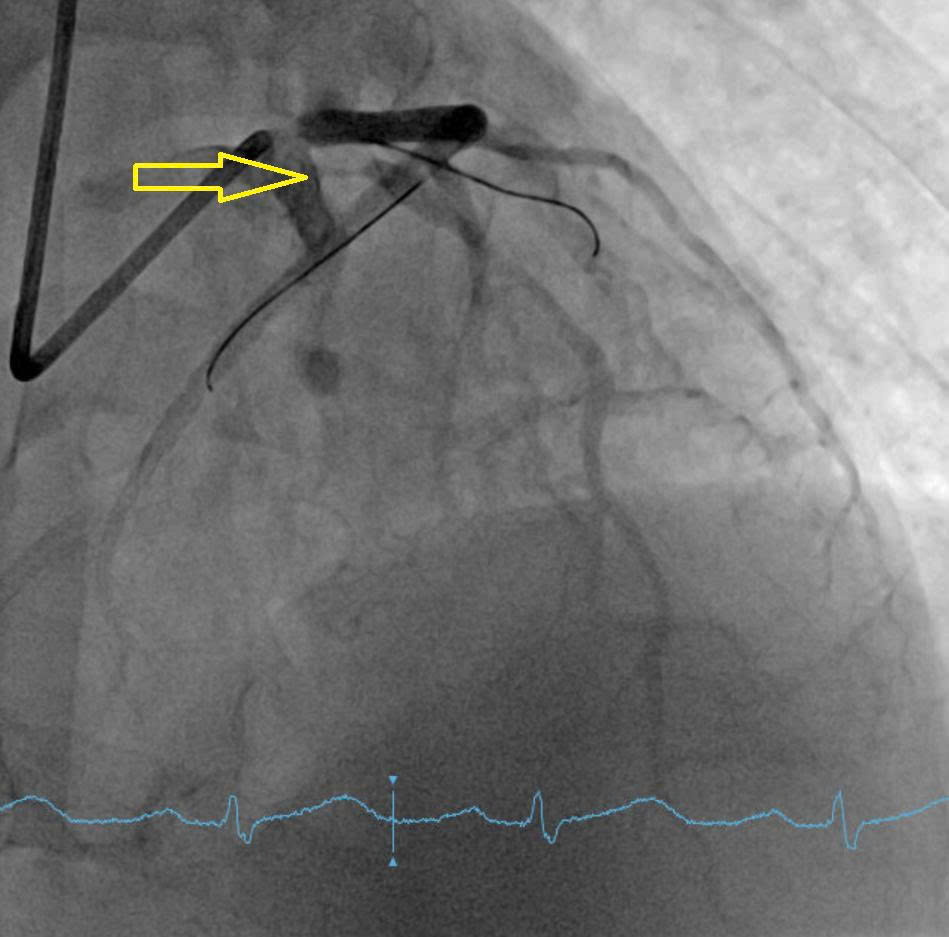

Engage the guiding catheter into the LCX ostium and advance a wire for anchoring in the LCX. After withdrawing the guiding catheter from the ostium and performing coronary angiography, it was observed that the LAD ostium originated separately from the LCX ostium and was located lower in the RAO–CRA view.Multiple attempts to selectively wire the LAD ostium using a 6 F SPB 3.0 guiding catheter (Asahi, Japan) from outside the LAD ostium were unsuccessful. The guiding catheter was then exchanged for a 6 F JL 3.5, and a Sion Blue wire was successfully advanced through the LAD ostium into the distal segment.DSA and IVUS post-intervention showed minimal stent area of 8.83 mm2, reached 112 % of distal reference vessel diameter. Stent covered LAD ostium with an area of 9.64 mm2 and was 2 mm inside the aortic artery. There was no protrusion, no dissection.